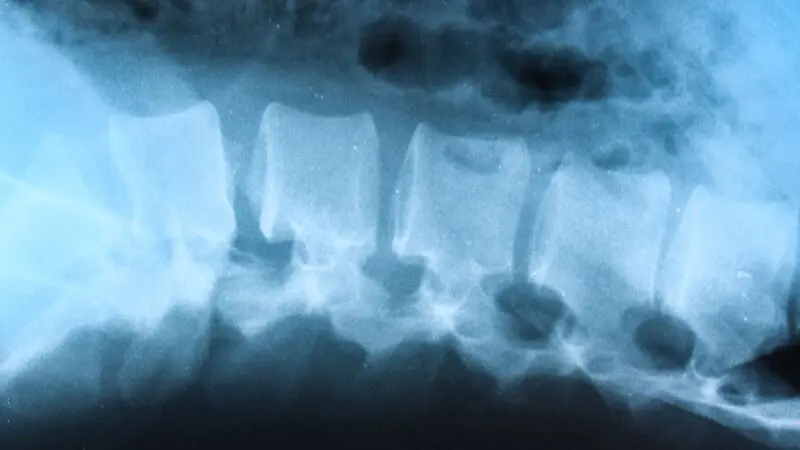

Morbus Bechterew ist eine chronisch-entzündliche Erkrankung des Skelettsystems, die vor allem die Wirbelsäule betrifft. Die Erkrankung führt zu Versteifungen der Gelenke, was zu Schmerzen und Bewegungseinschränkungen führen kann. Obwohl Morbus Bechterew eine chronische Erkrankung ist, beeinträchtigt sie nicht unbedingt die Fruchtbarkeit.